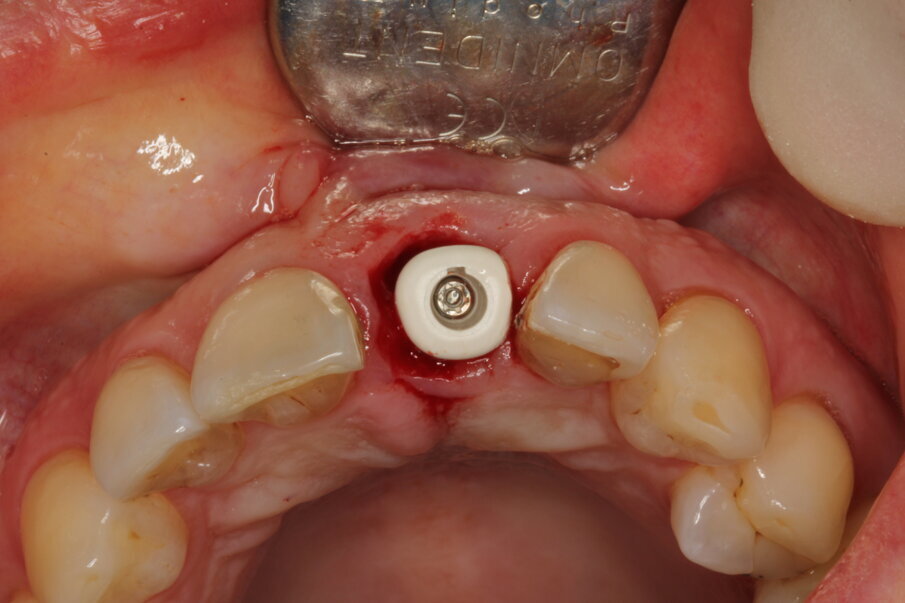

Local anaesthesia was performed with 2% mepivacaine with 1:100,000 adrenaline. Preventative antibiotic therapy with amoxicillin (1 g, b.d. for five days) was prescribed, aided by use of a 0.2 % chlorhexidine mouthrinse three times a day for one minute. The tooth was extracted and the sulcular epithelium removed with diamond burs. The milled surgical template (Figs. 12 & 13) served as a guide for the first 2 mm diameter pilot drill (Fig. 14). Thus, the planned depth, position and angulation of the osteotomy were obtained. The drill sequence was completed freehand, using tapered 3.0 and 3.4 mm drills. A Neoss Pro- Active Tapered Implant of 4 mm in diameter and 13 mm in length was inserted flush with the mesial/palatal/distal bone, motor driven up to a torque of 50 Ncm and then with a manual wrench (Fig. 15). The correct position of the internal hex was verified by checking the references on the implant driver, which ideally points in the buccal direction. Resonance frequency analysis with Penguin RFA (Integration Diagnostics Sweden) determined an ISQ value of 73/76. At this stage, a Neoss Esthetic Healing Abutment with a ScanPeg was connected to the implant (Fig. 16). A flap was then raised after a vertical incision of the frenulum and the expected buccal exposure of the implant neck was evident. Autogenous bone harvested from the drills was positioned directly on the implant surface (Fig. 17), followed by a bone substitute on top of it and on the buccal cortical bone (Fig. 18). This material was covered with a resorbable membrane (Fig. 19). The mobilised flap was then repositioned by rotating it coronally and fixed with single sutures (Fig. 20). The removable partial denture was adapted and delivered (Fig. 21). An immediate postoperative CBCT scan of 60 x 60 mm was performed, and it confirmed a perfectly centred implant position (Figs. 22 & 23).

Eight days after surgery, the patient reported that healing was uneventful and the prosthodontist removed the stitches. It has become the author’s standard protocol to perform an intraoral scan for implant position in this same session (Figs. 24 & 25). The specific and unique PEEK healing abutment used has an internal circular channel and on one side, normally positioned on the buccal aspect, a vertical rectangular slot (Fig. 26). After removing the PTFE tape used to plug this area during surgery, a ScanPeg can be positioned inside the healing abutment. This allows for a unique scanning procedure without removing the healing abutment, thus avoiding disturbing healing tissue or dislocating recently placed biomaterials. The producer provides libraries for STL files of the five different anatomical shapes—wide incisor, narrow incisor, canine, premolar and molar—that determine the basic profile of the gingival tunnel during healing.